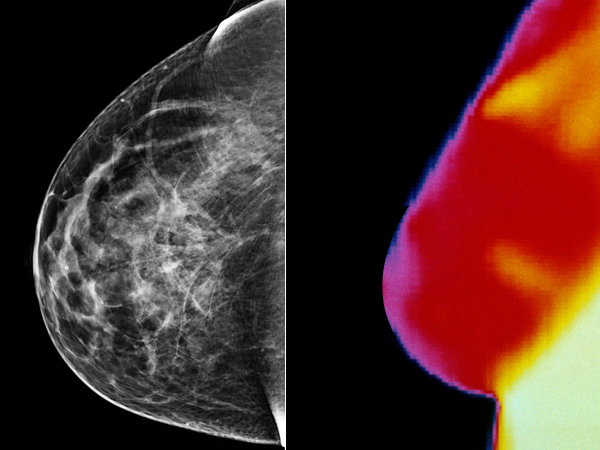

World Cancer Day 2022: Breast Cancer Detection And Mammography Vs Thermography

In recent years, there has been a lot of deliberation over the accurate method for breast cancer detection. The screening methods help detect and identify breast cancer in women who have no physical symptoms. It helps in the detection of cancerous growth in the early stage, thereby providing the opportunity to get treatments, at the right time. The debate over the effectiveness of the two tests, mammography and thermography are still ongoing with a larger section recommending mammography [1] .

Mammography involves the compression of the mammary gland between two plates and an X-ray is transmitted through the breast tissue [2] . So, it is basically an x-ray picture of the breast. Mammography helps to detect the development of breast cancer in women who have no signs or symptoms of the disease, as well as any lump or other signs of breast cancer.

The images captured during the process are called mammograms, which is then used by the doctor to detect any tumour growth or abnormalities in the mammary glands [3] , [4] . Mammographies are recommended for younger women as well, who have symptoms or are at a high risk of developing the condition [5] .

Also termed as infrared imaging of the breast, breast thermography or thermography detects and records temperature changes on the surface of the skin. Thermography uses an infrared camera to detect heat patterns and blood flow in body tissues. DITI or digital infrared thermal imaging is the type of thermography that is used in the detection and diagnosis of breast cancer. It helps in understanding the temperature differences on the surface of the breasts; which help detect the cancerous growths on the mammary gland [13] , [14] .

Before beginning the test, you will be required to be acclimated to the room temperature. Your body has to be in line with the room temperature to avoid the difference in your body temperature and room temperature. Then, you will be required to stand in front of the imaging system, and the technician will take a series of six images, including front and side view of your breasts [15] . The images will show areas of different temperature in the breasts and display it in the form of a heat map. The cancerous cells have a higher temperature than the surrounding tissue because, they grow more blood vessels and has more blood flow, and have higher metabolic rates than normal cells [14] .

Thermography uses temperature differences to identify cancerous growths. The excessive formation of blood vessels and inflammation in the breast tissue will show up on the infrared images as areas with a higher temperature than the surrounding areas [15] , [16] . Some women choose thermography because it does not involve being exposed to radiation or being squished by a machine. The test takes around 30 minutes and once the analysis is carried out, the results will be given to you in a period of 10-15 days.

Mammography Vs Thermography

The debate over mammography and thermography for effective cancer detection has been ongoing for some time now. The benefits and the limitation pertaining to both types of tests have incurred the confusion of choosing the most effective as well as safe method. And, the reminder from the U.S. Food and Drug Administration (FDA) which states that thermography is in no way a substitute for mammography [20] . The larger section tends to think that, as thermography doesn't touch your skin or compress your breast like a mammogram, and has no radiation - it is the best suitable option [21] .

However, FDA is adamant and determined on spreading awareness on the dilemma by clarifying that thermography is in no way a better measure than mammography. On February 25, 2019, FDA issued a safety warning to women, patients recommended for breast cancer screening, healthcare providers, and cancer treatment advocacy organizations that thermography should not be used in place of mammography to detect, diagnose, or screen for breast cancer [22] .